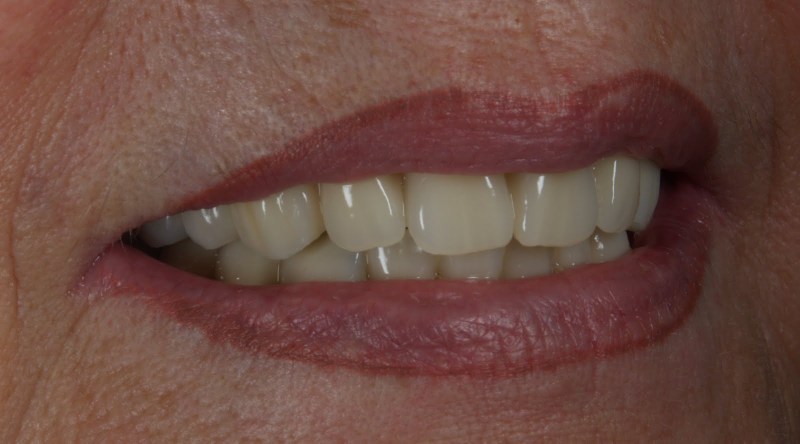

Patientenzufriedenheit